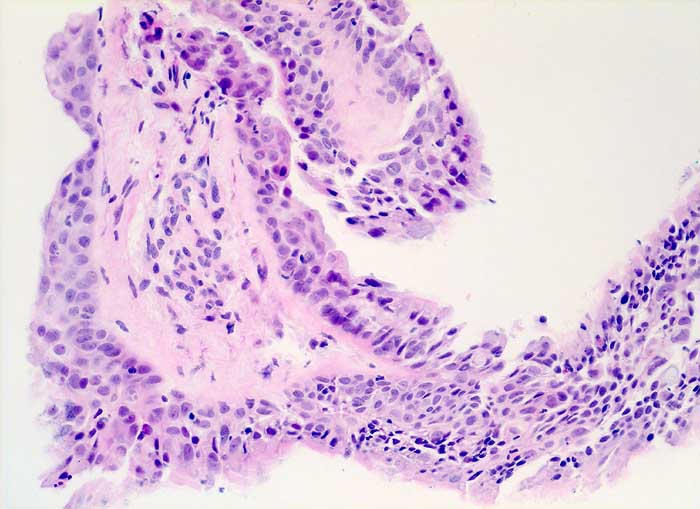

Strahleninduzierte Kernatypien

Nach Strahlentherapie eines mediastinalen Tumors oder eines Bronchuskarzinoms zeigen Bronchial- und Alveolarepithel ähnliche Kernveränderungen wie nach Zytostatikatherapie. Die Flimmerzellen haben unterschiedlich stark vergrösserte oft hyperchromatische und entrundete Kerne, sowie fragiles Zytoplasma. Der Nachweis von Flimmerhaaren und die erhaltene Kern-Zytoplasmarelation sprechen für reaktiv veränderte Bronchialepithelien.